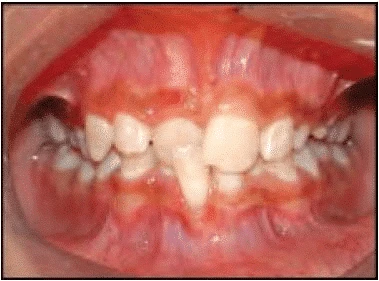

Khám răng

- Kiểm tra tình trạng răng như số răng hiện có, răng chưa mọc hoặc mất răng.

- Những bất thường về răng và khớp cắn cần được ghi lại một cách chi tiết. Điều trị răng sâu trước khi bắt đầu chỉnh nha. Kiểm tra bộ răng xem có bị dị tật gì khác không, thiểu sản, có mang phục hồi, mòn răng và đổi màu răng.

- Đánh giá khớp cắn:

- Tương quan răng cối lớn là hạng I, II hay III

- Độ cắn chìa và cắn phủ: cắn sâu hay cắn hở

- Có trượt chức năng hoặc cắn chéo

- Đường giữa mặt có trùng với đường giữa răng hay không.

- Vị trí các răng có gì bất thường như xoay răng, thay đổi vị trí hoặc nứt răng.

- Hình dạng và sự đối xứng của cung răng trên và cung răng dưới.